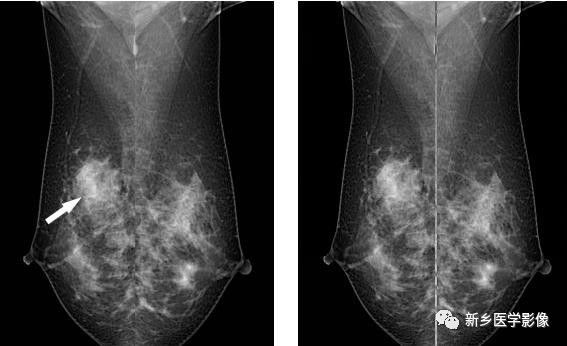

乳腺良性钙化X线图像

右乳CC位片示腺体内见散在颗粒状、小环形钙化(白箭)

乳腺恶性钙化X线图像

A和b. 右乳MLO位和CC位片示外上象限见密集细小砂粒状,呈簇状钙化(白箭)

乳腺局限性不对称致密(乳腺癌)X线图像

a和b. 右侧和左侧双乳MLO位片示右乳外上象限见片状不对称致密影,伴小砂粒状,呈簇状钙化(白箭)